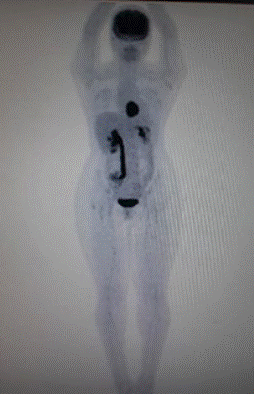

La paciente fue hospitalizada para confirmación bioquímica de tumor secretor de catecolaminas. Durante el examen físico estuvo clínicamente estable, con cifras tensionales de 138/64 mmHg, frecuencia cardiaca de 92 latidos por minuto y no hubo otros hallazgos relevantes. Los estudios bioquímicos confirmaron una producción excesiva de catecolaminas con un fenotipo noradrenérgico en sangre y orina (tabla 1), y el FGD-PET/TC reportó una lesión hipermetabólica en mediastino posterior (figura 2). Se indicó una secuenciación de exoma completo individual que identificó una variante heterocigota en el gen succinato deshidrogenasa subunidad B, variante c166_170del, de significado patogénico.

Estudio con PET/TC. Lesión hipermetabólica en mediastino posterior

Figura 2: Estudio con PET/TC. Lesión hipermetabólica en mediastino posterior

Fuente: elaboración propia.